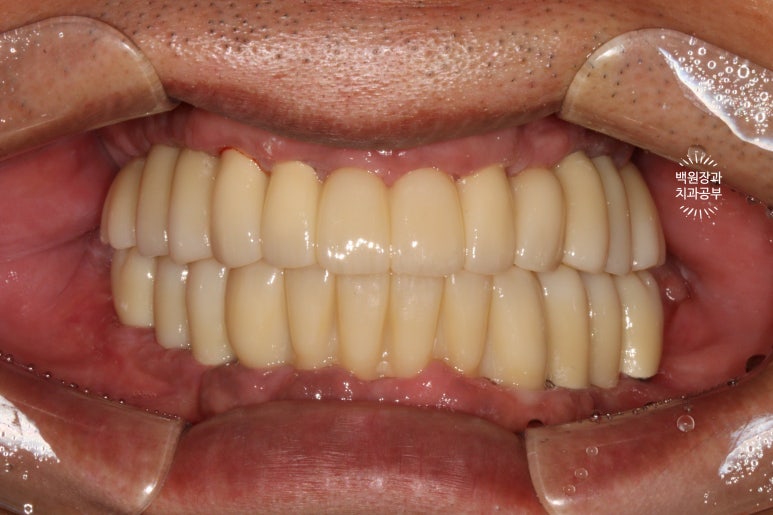

시간이 지나.. 최종 보철물을 만들어드리는 시간입니다.

약 한달간의 씹는 연습을 마치게 되면, 이제 본격적으로 최종 보철물을 제작해드리게 됩니다.

지르코니아 재질로 만들어진 크라운은 심미적으로도 유리하며, 그 단단함은 성인 남성이 넉넉히 사용하여도 깨지지 않을 정도에요.

치아 색이 약간 노랗다 생각하실수도 있으나, 피부색에 맞추어 제작되므로 너무 걱정하진 마세요!

오히려 너무 밝은 하얀 치아가 어색한 분도 많이 있으시기 때문입니다.